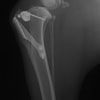

術前左後肢側面像

術前正面像

手術前後のTPA(脛骨高平部の角度)を測定しています。

約29°から約10°へ矯正されています。

本症例は、走った後に左後肢を挙上していることを主訴に来院されました。触診時に左膝関節のクリック音を聴取、レントゲン検査にて左脛骨の前方変位が認められました。術中に、前十字靱帯の断裂及び内側半月板の損傷、内側の軟部組織の顕著な腫脹を確認。半月板切除、TPLOを実施しました。周囲組織への炎症の波及もあったため回復に時間を要しておりますが、徐々に跛行頻度は減少傾向にあり、現在も経過観察中です。術前に約29°あったTPAは術後に約10°まで矯正されました。